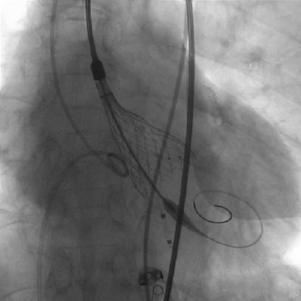

手术过程

患者麻醉方式采取全麻,建立静脉通路后,穿刺左侧股动脉,建立副入路。在超声引导下精准穿刺右股动脉及股静脉,预埋两把ProGlide缝合器,置入20F动脉鞘管,漂浮电极经股静脉送至右室心尖。跨瓣成功后,将Lunderquist导丝送入左心室, 23mm球囊预扩张,Venus-A 29瓣膜精准定位并释放,术中造影及超声反馈良好,瓣膜形态良好,结果满意。

主动脉根部造影

球囊预扩